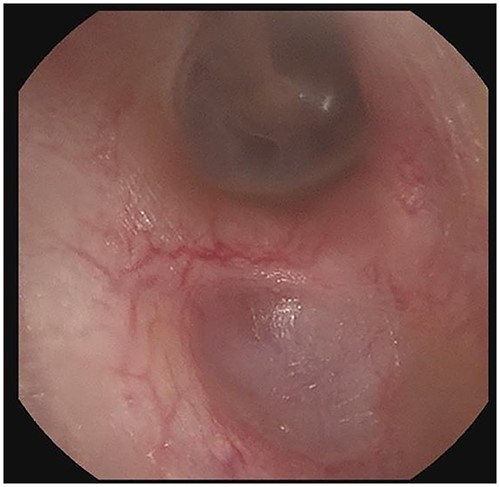

Panel a shows the indentation of the left external auditory canal with bony sequestration. Picture was after debridement. Panel b shows the right external auditory canal. Less extensive than the left, however, fragmentation and sequestration is also seen.

Patient B, a 56-year-old male, was initially diagnosed in 11/2019 and has been consistently followed for 35 months. He was also referred for cerumen impaction in the left ear canal, associated with otorrhea and hearing loss. He was diagnosed with an erosive indentation in the inferior wall of his external auditory canal, filled with ceruminous debris and minimal amount of drainage. Albeit minor, there was obvious bony sequestration in the area of the lesion and miniscule osseous fragments were retrieved from the indentation with a microsuction (Fig. 3a). He was initially followed every 6 months, but his serial debridement was eventually adjusted to every three months, due to his more severe clinical presentation. His symptoms remained mild at all times, including mild intermittent otorrhea on the left side, which was treated as it occurred, with a short course of ototopic quinolone. Interestingly, the patient was noticed to have a similar but smaller lesion (erosive indentation in the inferior wall of his external auditory canal) on the contralateral side, which was managed on the same manner with serial debridements (Fig. 3b). Patient B has also no history of diabetes or osteoporosis. He has an asymptomatic septal perforation, attributed to remote history of vasoconstrictive substances abuse. His blood pressure medications include amlodipine, also used for prolonged intervals. He has satisfactory control of his symptoms with frequent debridements, especially after his follow-up frequency was increased to every three months.